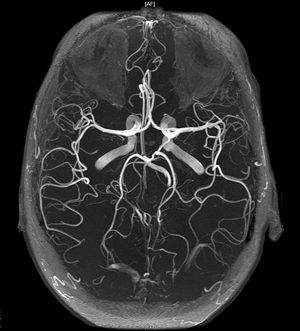

The Circle of Willis is an arterial polygon formed as the internal carotid and vertebral systems anastomose around the optic chiasm and infundibulum of the pituitary stalk in the suprasellar cistern. This communicating pathway allows equalization of blood-flow between the two sides of the brain, and permits anastomotic circulation, should a part of the circulation be occluded. It's named after Thomas Willis. (1621-1675)